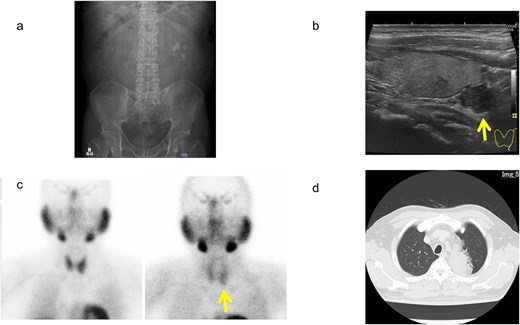

A man in his 50s presented to our hospital with a 1-month history of left lumbar back pain. He had a smoking history of 40 cigarettes per day from age 20 until the time of his hospital visit. He had no history of pancreatic tumors and no specific family history. Kidney–ureter–bladder radiography and computed tomography (CT) revealed a left ureteral calculus (23 mm × 17 mm) and a right renal calculus (Fig. 1a). Blood tests showed hypercalcemia (11.0 mg/dL; normal range: 8.8–10.1 mg/dL) and elevated intact-parathyroid hormone (PTH) (202 pg/mL; normal range: 10–65 pg/mL) levels. The urinary calcium-to-creatinine (Ca/Cre) ratio was elevated at 0.3. Cervical ultrasonography showed a well-defined adenoma in the left inferior thyroid, measuring 18 mm × 12 mm, and we consulted with the Department of Endocrinology and Metabolism (Fig. 1b). 99mTc-methoxy isobutyl isonitrile scintigraphy showed accumulation at the same site during the delayed phase, and a parathyroid tumor was suspected (Fig. 1c).

Imaging findings of urinary calculus, as well as parathyroid and lung lesions. (a) Kidney–ureter–bladder radiograph. (b) Ultrasonography of the cervix. (c) 99mTc-methoxy isobutyl isonitrile scintigraphy. (d) Chest computed tomography. Arrows indicate tumor areas.